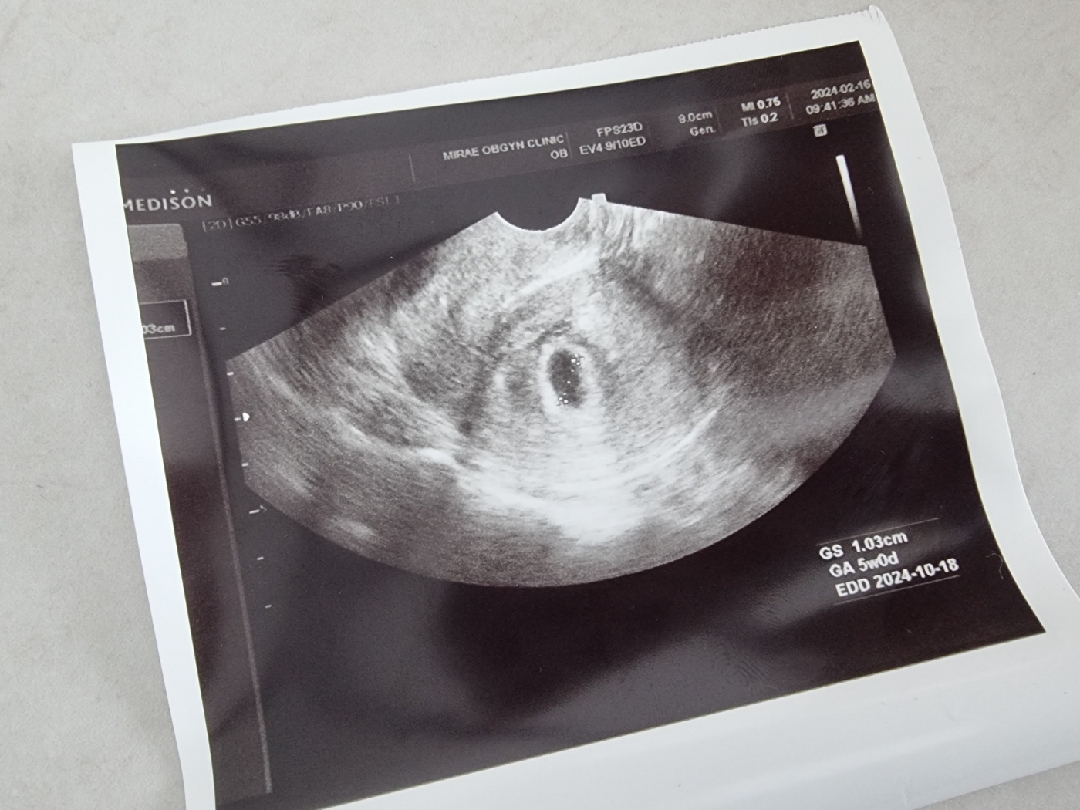

오늘 병원가서 아기집보고왔어요!ㅎㅎ 선생님께서 예쁘게 자리잘잡았다고 해주셨어요 유산경험이 있는지라 너무 걱정많았는데 선생님말씀에 안심되었어요!ㅎ 자리잘잡았나요?ㅎ

저도 오늘 5주 0일차인데 첫 초음파로 아기집 보고왔네요~! 너무 축하드려요!! 저희 심장소리 까지 화이팅 해보아요~!